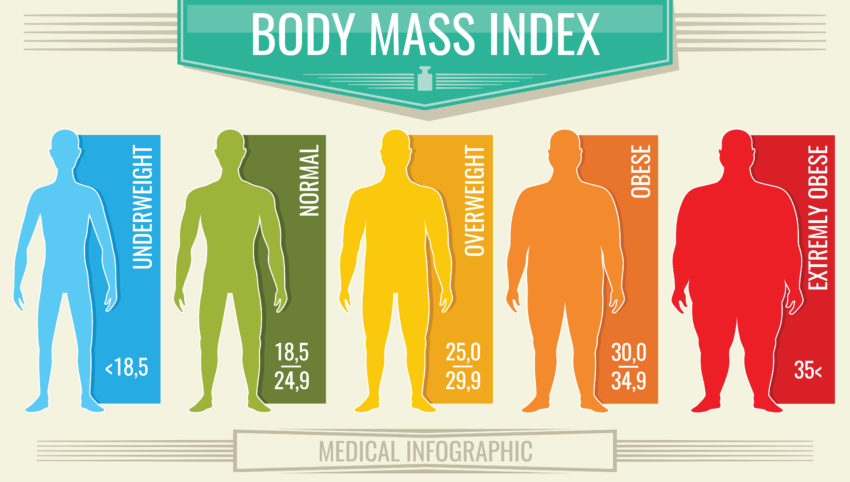

Pour les adultes, l’indice de masse corporelle est égal au poids (exprimée en kilogrammes) divisé par le carré de la taille de la personne (en mètres) : Exemple pour 75 kg et 1,75 m : IMC = 75 / (1,75)2 = 24,49

• Un IMC entre 18,5 et 25 est considéré comme normal chez un adulte.

• Entre 25 et 30, on parle de surpoids (surcharge pondérale).

• Au-delà de 30, on parle d’obésité.

• De 35 à 40, on parle d’obésité sévère et, au-delà de 40, d’obésité morbide.

L’IMC n’est qu’un outil parmi d’autres, il ne doit et ne peut en aucun cas être utilisé seul. Une estimation du pourcentage de masse grasse est d’ailleurs souvent plus représentatif notamment pour les sportifs.